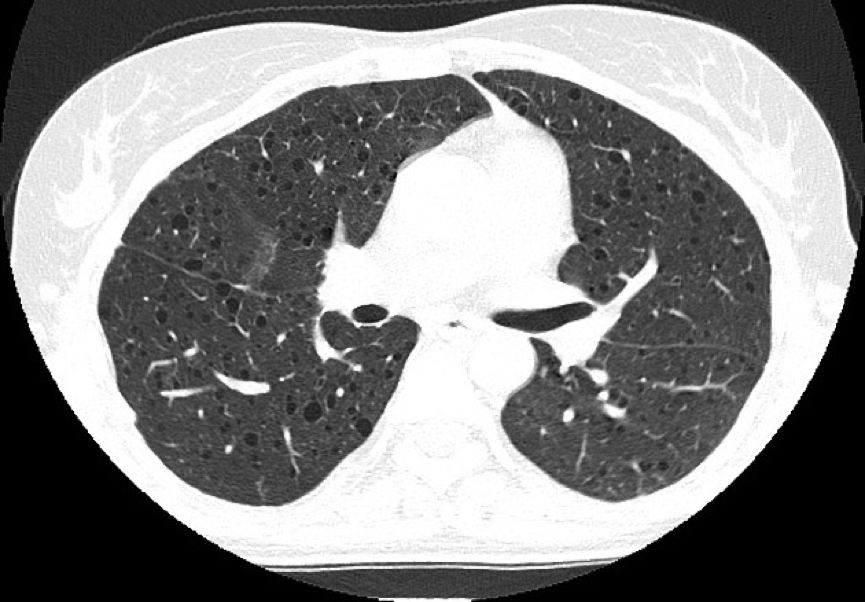

外院肺功能检查提示:阻塞性通气功能障碍。HRCT显示双肺弥漫性分布类圆形薄壁囊状阴影,囊壁较光滑,囊腔大小不等,多数在2~10 mm之间,右侧胸腔内见气体影。纵隔结构清楚,未见肿大淋巴结。

常规CT表现为两肺密度减低,体积增大,呈肺气肿样改变。HRCT对本病的早期诊断及病情发展的监测有重要意义,其特征性改变为两肺广泛弥漫性分布的薄壁小囊状病变,两侧对称,无上中下肺野的区别,也无中央性与周围性的分布差异。囊腔直径为2~30 mm,大多数直径小于10 mm,囊壁厚度多小于2 mm。